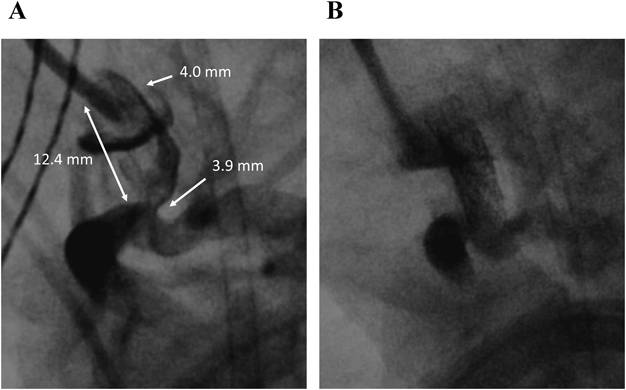

症例3は,TGA/VSD/PS,右室軽度低形成,単一冠動脈で,二心室修復の境界域であった.DSにより段階的に心室容量増加を促し,初回手術をRastelli手術とすることを目標とした.チアノーゼが増強したため,日齢29,体重3.3 kgでバルーン心房中隔裂開術(Balloon atrial septostomy: BAS)および,左総頸動脈穿刺によるDSを施行した.動脈管は屈曲・狭窄していたが,Integrity™ 3.5×9.0 mm(Medtronic Inc; Santa Rosa, CA)を留置し直線的な開大を得た(Fig. 4).治療後は経皮的酸素飽和度(SpO2)が70%から90%に上昇し,高肺血流性心不全に対する内科的治療後に退院した.その後,体重増加に伴いSpO2が再び70%台まで低下したため,生後3か月,体重5.1 kgでステント追加の方針とした.体格の成長に伴い,動脈管へのアプローチは右大腿動脈から右室経由で順行性に到達した.MULTI-LINK 8® 4.0×12.0 mm(Abbott; Chicago, IL)を追加し,SpO2は81%に上昇した.ステント追加により,段階的な心室,特に右室容量の増加(日齢3→生後8か月:心胸郭比0.51→0.63,右室拡張末期面積係数15.9 cm2/m2→23.2 cm2/m2)が達成できたため(Fig. 5),生後8か月,体重6.4 kgでRastelli手術に到達した.

Pediatric Cardiology and Cardiac Surgery 36(4): 294-305 (2020)

Fig. 4 Case 3: DS for TGA/PS

A) Lateral view of ductus arteriosus angiography revealed vertical and tortuous ductus arteriosus originating from transverse aortic arch. B) Angiography after DS. PS: pulmonary artery stenosis, TGA: transposition of great artery